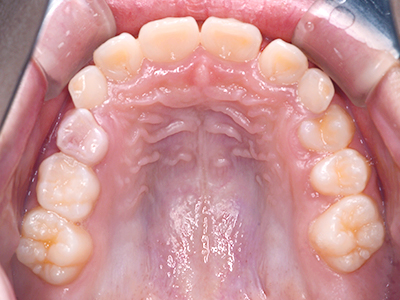

歯並びの相談に来られるお子様は、口呼吸をしているケースが多く、これが歯並びに大きな影響を与えています。

- 口呼吸をしている

↓ - 舌の位置が悪くなる

↓ - 頬の圧力が上の歯列にかかりやすくなる

↓ - 上あごが狭くなる

↓ - 下あごが狭くなる・下あごの位置が悪くなる

↓ - さまざまな不正咬合が生じる

ないき歯科クリニックでは、上あごの成長不足を補い、鼻呼吸を獲得しつつ歯列を整え、将来のお口をより健康な状態にすることをゴールに定める矯正治療をおこなっています。